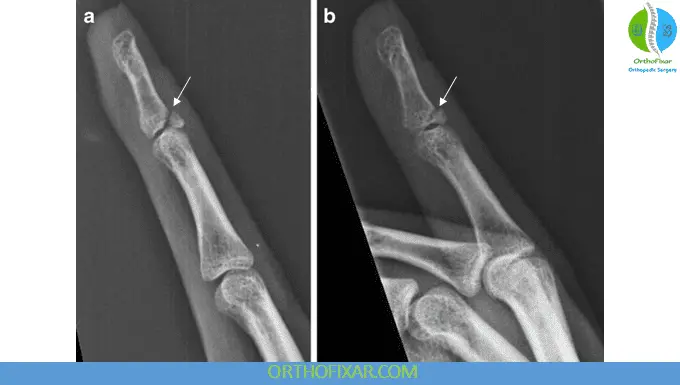

Imaging

- X-rays are essential to:

- Identify avulsion fractures

- Assess joint alignment

- Detect subluxation of the DIP joint

Classification

Common classification systems include:

- Soft tissue vs. bony mallet

Doyle’s Classification of Mallet Finger Injuries

| Type I | Closed injury with or without small dorsal avulsion fracture |

| Type II | Open injury (laceration) |

| Type III | Open injury (deep soft tissue abrasion involving loss of skin and tendon substance) |

| Type IV | Mallet fracture: A = distal phalanx physeal injury (pediatrics) B = fracture fragment involving 20% to 50% of articular surface (adult) C = fracture fragment >50% of articular surface (adult) |